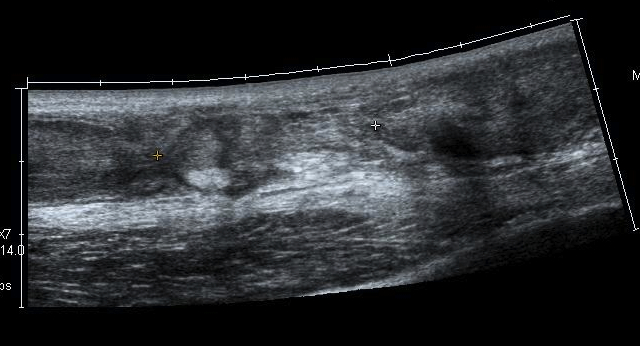

Ultrasound

Diagnose rupture and check reduction of tendon ends with plantarflexion

Aminlari et al J Emerg Med 2021

- systematic review

- ultrasound 95% sensitive and 99% specific for complete rupture